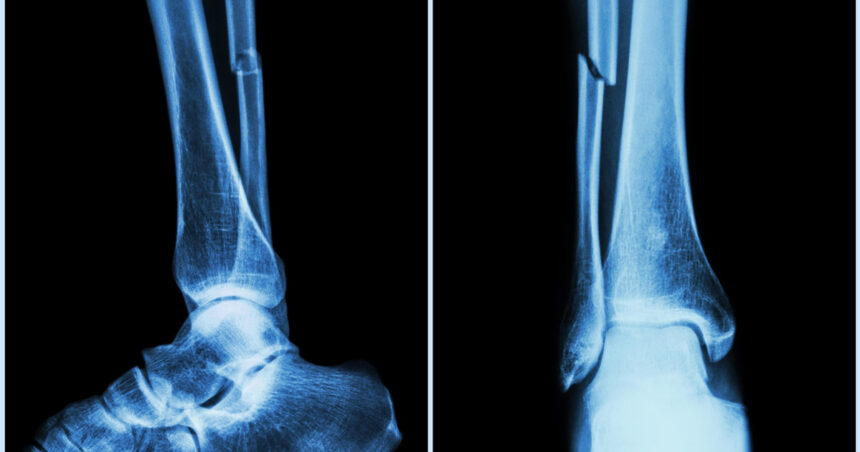

Fracturi vindecate în câteva minute: un lipici pentru oase, soluția găsită de cercetătorii chinezi

Cercetătorii din provincia Zhejiang, sub conducerea medicului ortoped dr. Lin Xianfeng de la spitalul Sir Run Run Shaw, au creat un adeziv osos inovator care poate trata fracturile și fragmentele osoase zdrobite în doar trei minute. Această substanță, denumită „Bone-02”, promite să schimbe radical abordarea tradițională în tratarea fracturilor, reducând necesitatea intervențiilor chirurgicale invazive și a implanturilor metalice.

Adezivul este inspirat de modul în care stridiile se aderă ferm la suprafețe sub apă, încercând să reproducă acest mecanism pentru fixarea oaselor fracturate. Potrivit dr. Xianfeng, adezivul reușește să fixeze fragmentele osoase chiar și în medii bogate în sânge, întâlnite în timpul operațiilor.

Un avantaj semnificativ al „Bone-02” este că se absoarbe natural în organism pe măsură ce osul se vindecă, eliminând necesitatea unei a doua intervenții pentru îndepărtarea implanturilor. Testele de laborator și primele încercări clinice au arătat atât siguranță, cât și eficacitate, procedura fiind realizată în mai puțin de trei minute în comparație cu tehnicile convenționale.

Formula adezivului combină compuși de calciu și proteine specifice, asigurând o legătură puternică și flexibilă. Aplicarea sa necesită doar o incizie minimă, prin care adezivul este introdus direct în zona fracturată, sigilând fragmentele osoase rapid.

Până în prezent, „Bone-02” a fost testat cu succes la peste 150 de pacienți, demonstrând o forță de lipire a oaselor de peste 180 de kilograme. Parametrii mecanici sugerează că acest adeziv ar putea înlocui implanturile metalice tradiționale. De asemenea, metoda ar putea reduce riscurile de reacții adverse și infecții post-operatorii.

Autoritățile sanitare chineze au aprobat dezvoltarea și aplicarea clinică a acestui adeziv osos, cu intenția de a-l introduce în spitalele din țară ca alternativă standard la chirurgia ortopedică. De asemenea, se evaluează capacitatea de producție industrială pentru export, iar China deține brevete naționale și internaționale pentru această tehnologie, pe care își propune să o facă accesibilă comunității medicale globale.